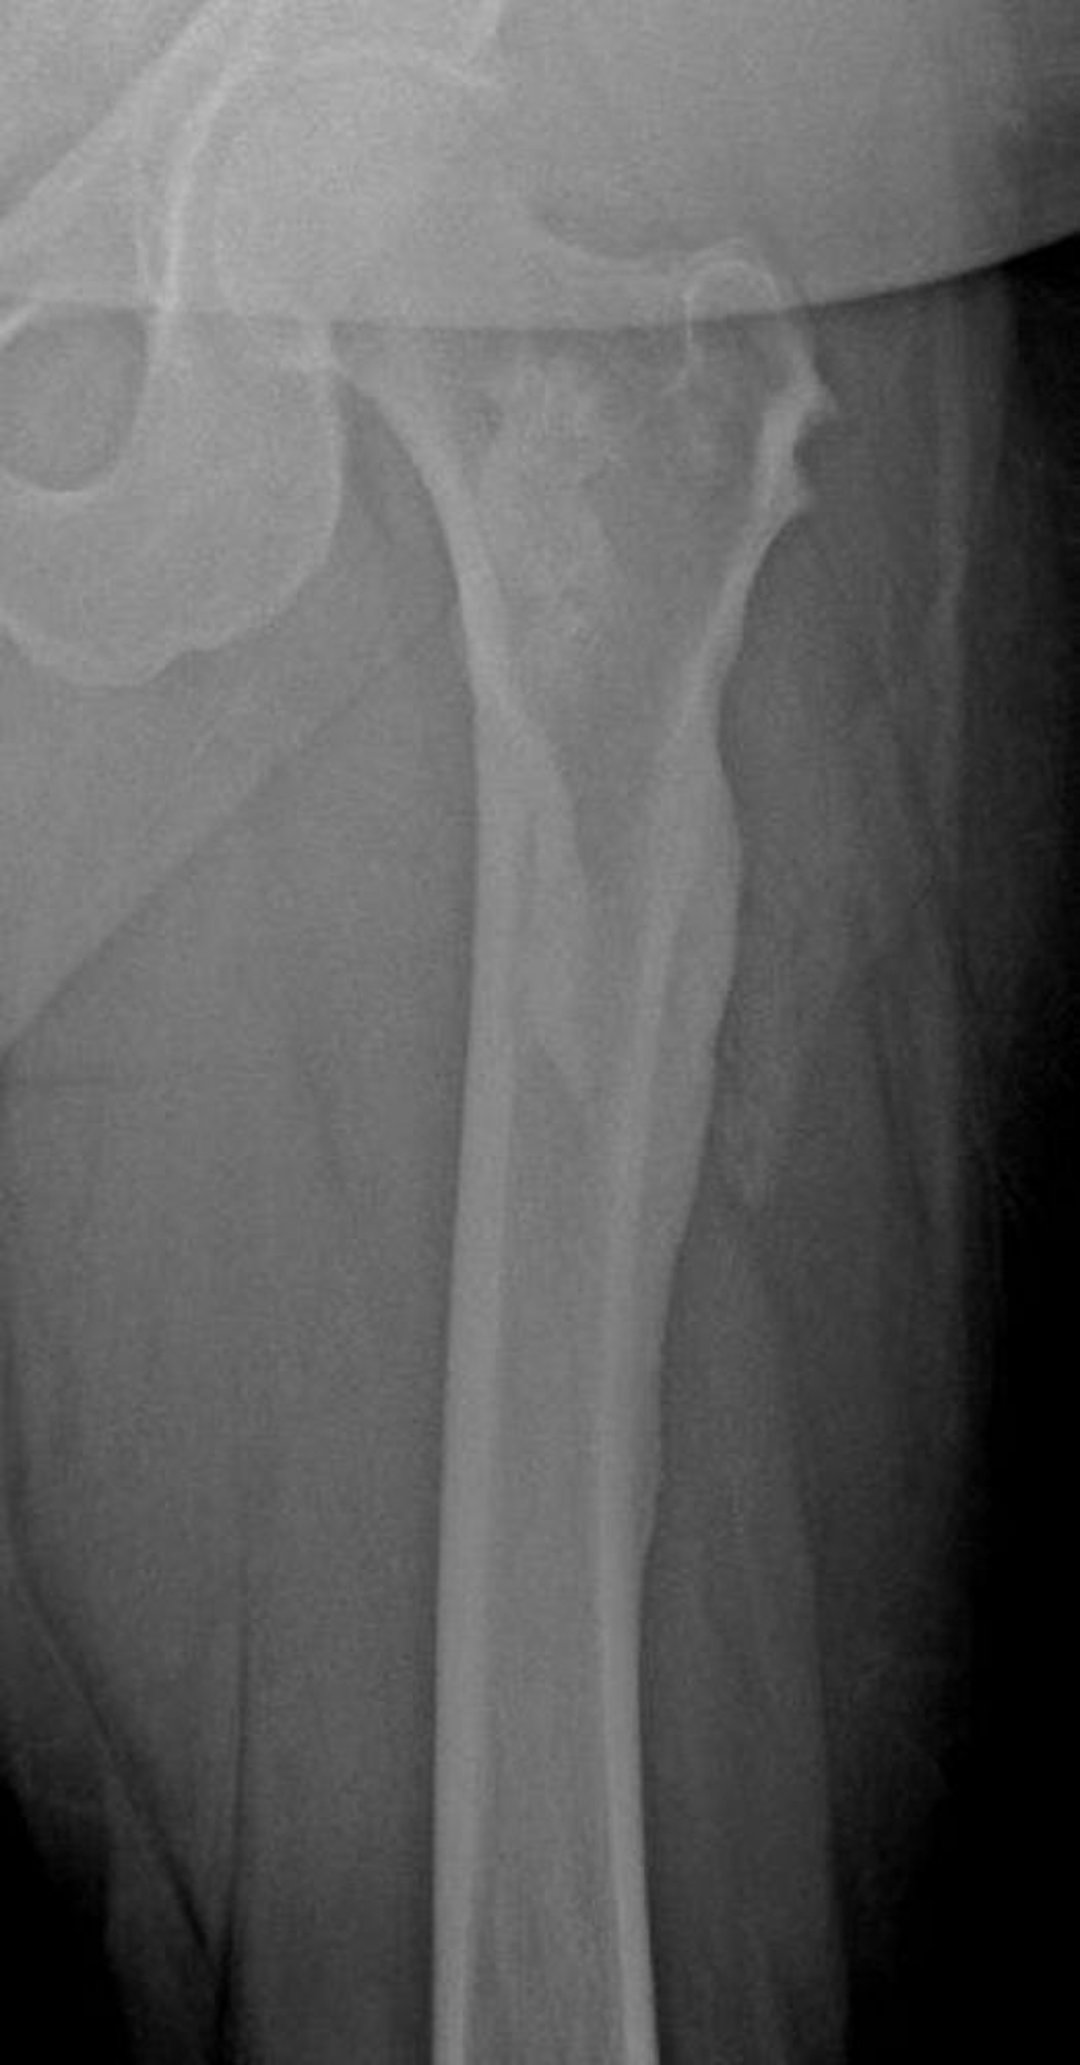

Melorreostosis (cera de vela que gotea)

Esta radiografía muestra la apariencia de "vela goteando cera" de la melorreostosis del fémur; es particularmente evidente en la corteza femoral lateral.

Image courtesy of Michael J. Joyce, MD, and David M. Joyce, MD.